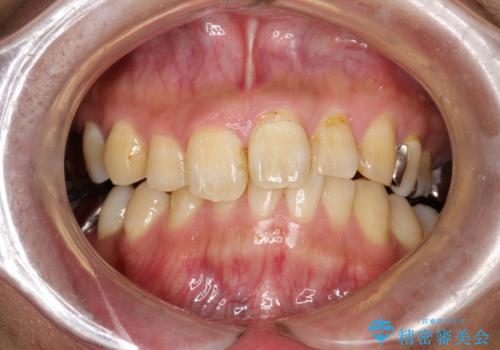

PMTCで歯の着色落とし

- 歯の着色・汚れが気になるとのことでクリーニンング希望とのことでした。PMTC30分コースを行いました。